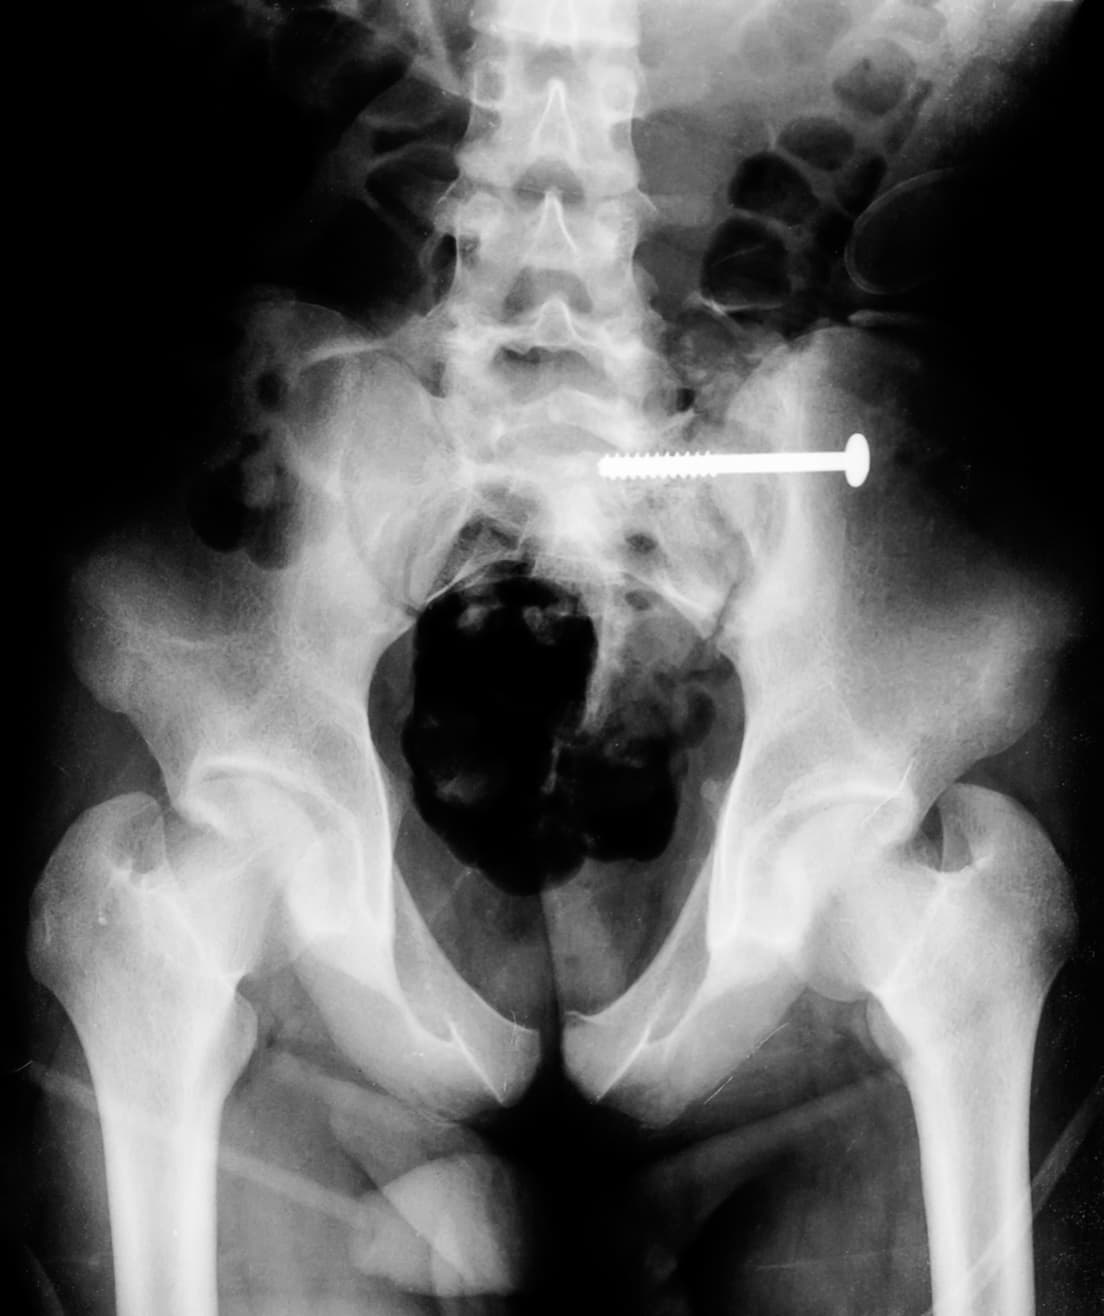

Medical mistakes with “unintended retained foreign objects” are among the nation’s top 5 causes of death and severe harm, noted the article. Such errors are estimated to take place in one out of 5,500 surgeries. Items left include surgical sponges, broken drill bits, tips of suture needles, guide wires, screws, and gauze. These objects can result in infections, permanent organ damage, loss of bodily function, and additional costly operations. Patients can suffer for years before the cause is known.

Pottstown resident Lauren Marsh had an emergency C-section. It was chaotic and rushed, and the nurse failed to count each sponge before the start. Afterward, the hospital missed the warning signs, which included an image of the sponge on a post-surgical x-ray, the patient’s complaints of abdominal pain, and a white blood cell count that signaled possible infection. She was in pain for months, until the sponge was discovered. It had invaded her intestines and damaged her bowels.